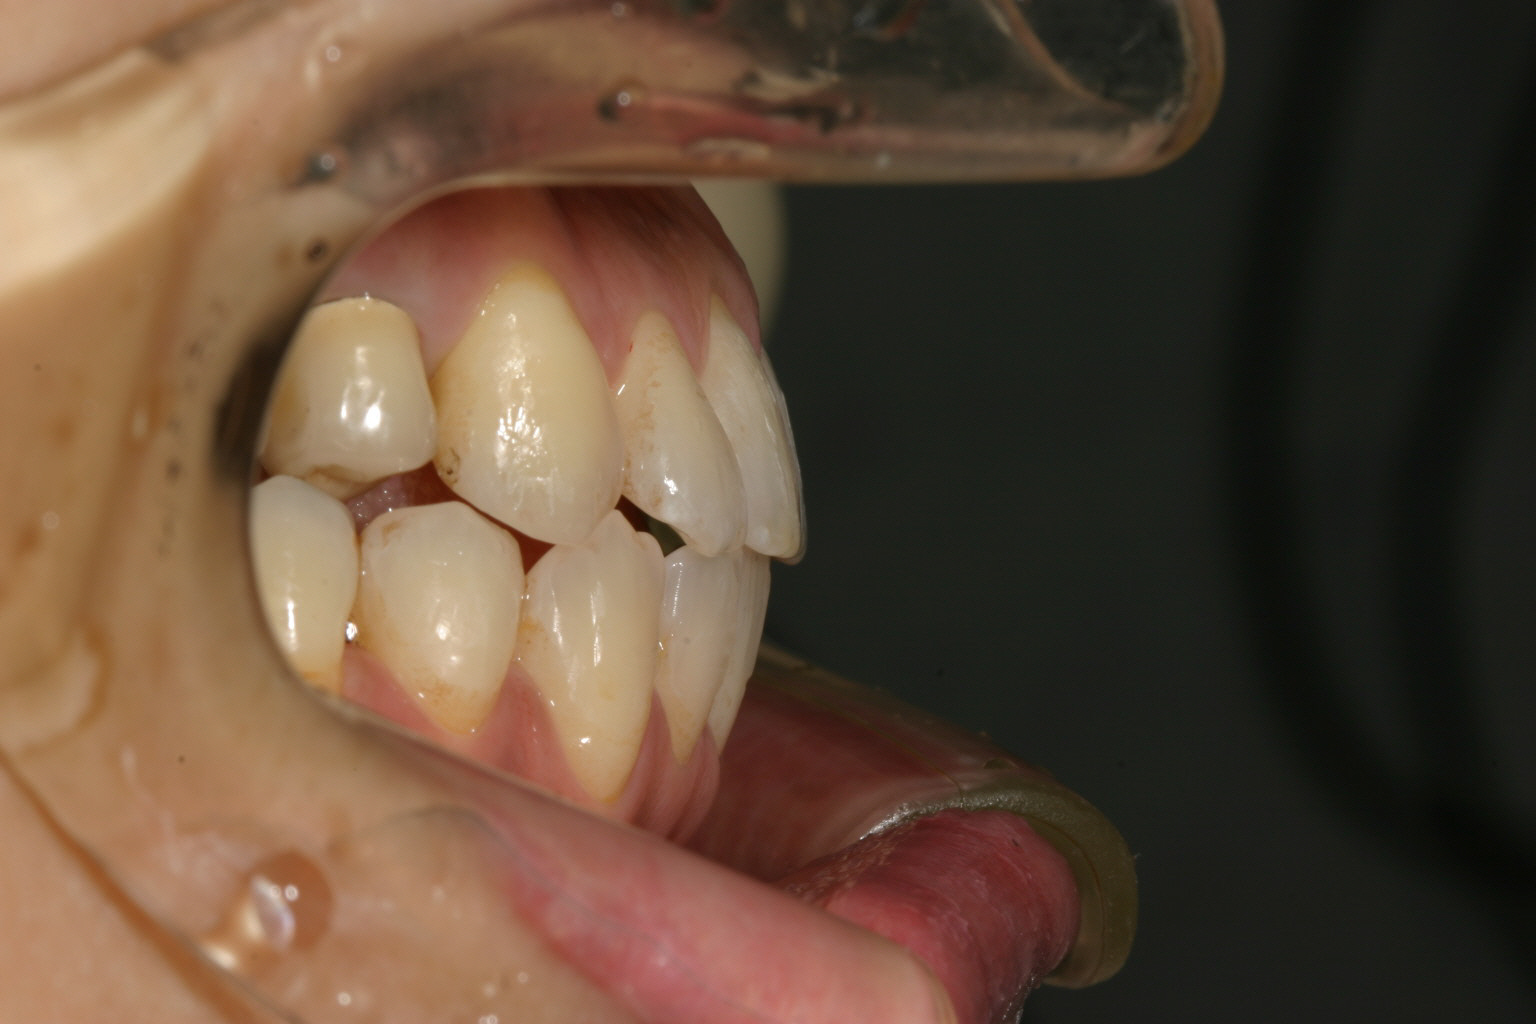

凄い開咬ですね~ この症例にはマルチループワイヤーしかありません。

今回のような超複雑な開咬症例にはマルチループワイヤーしかないでしょう。

前歯が開いているからと言って前歯をひっぱって閉じようとすると結果的に又開いてきます。

この症例では前歯を閉じたんじゃなく当たっている奥歯を顎の中にめり込ませたって感じで矯正行いました。その様な動きを短期間で行えるのはマルチループワイヤー以外考えられません。